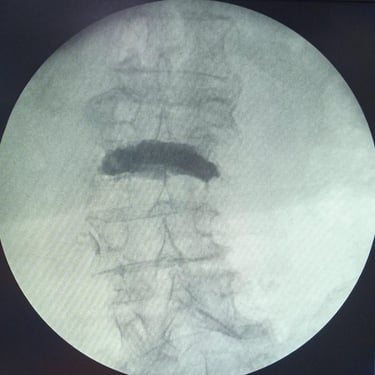

Fractura Lumbar Osteoporótica / Vertebroplastía y Bloqueo Lumbar Selectivo

La fractura lumbar osteoporótica y la artrosis lumbar son causas frecuentes de dolor crónico y limitación funcional en el adulto mayor. La osteoporosis debilita las vértebras, favoreciendo fracturas incluso ante esfuerzos mínimos, mientras que la artrosis genera desgaste articular e inflamación. La vertebroplastía percutánea permite estabilizar las vértebras fracturadas mediante la inyección de cemento óseo, proporcionando alivio rápido y mejorando la movilidad. En casos de dolor persistente por artrosis, el bloqueo lumbar selectivo ayuda a reducir la inflamación y el dolor. Ambas técnicas son procedimientos mínimamente invasivos que mejoran la calidad de vida y facilitan la recuperación funcional.